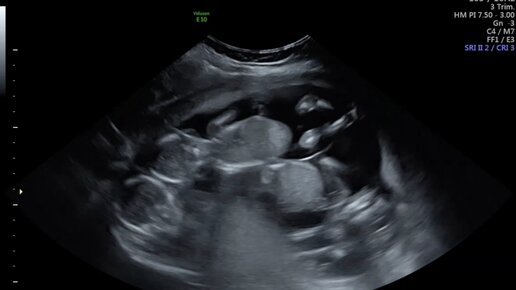

В самый короткий день 2022 года тест на беременность показал заветные || и я с нетерпением стала ждать подтверждающего беременность похода на УЗИ. 7 января был тот день, когда по сроку должно быть видно плодное яйцо и слышно сердечко ❤️ малыша. Тогда на узи я услышала радостную весть: беременность маточная, врач увидела и показала мне ОДНО плодное яйцо и дала послушать сердцебиение. Я выдохнула. Теперь оставалось только встать на учет в женскую консультацию и ждать первый скрининг. Так уж вышло,...